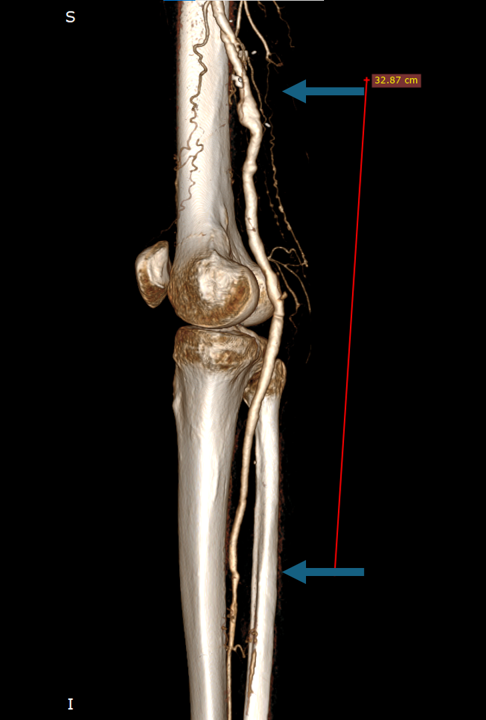

A CT angiogram showing the long-term result of a lower limb bypass graft in a now 71-year-old male patient. The image depicts a well-functioning above-knee popliteal artery to mid-anterior tibial artery bypass using autologous vein, tunneled deep.

The surgery was performed 8 years ago for critical limb ischemia. Today, the patient remains symptom-free, walks normally, and enjoys a fully active lifestyle. The graft is widely patent, with no evidence of stenosis or disease progression along its 32.87 cm course.

This case exemplifies the durability and efficacy of carefully planned and executed autogenous vein bypasses in select patients. Deep tunneling and optimal anastomotic technique have contributed to excellent long-term outcomes in this patient. No endovascular re-intervention has been necessary, and clinical follow-up continues to support the graft’s robustness.